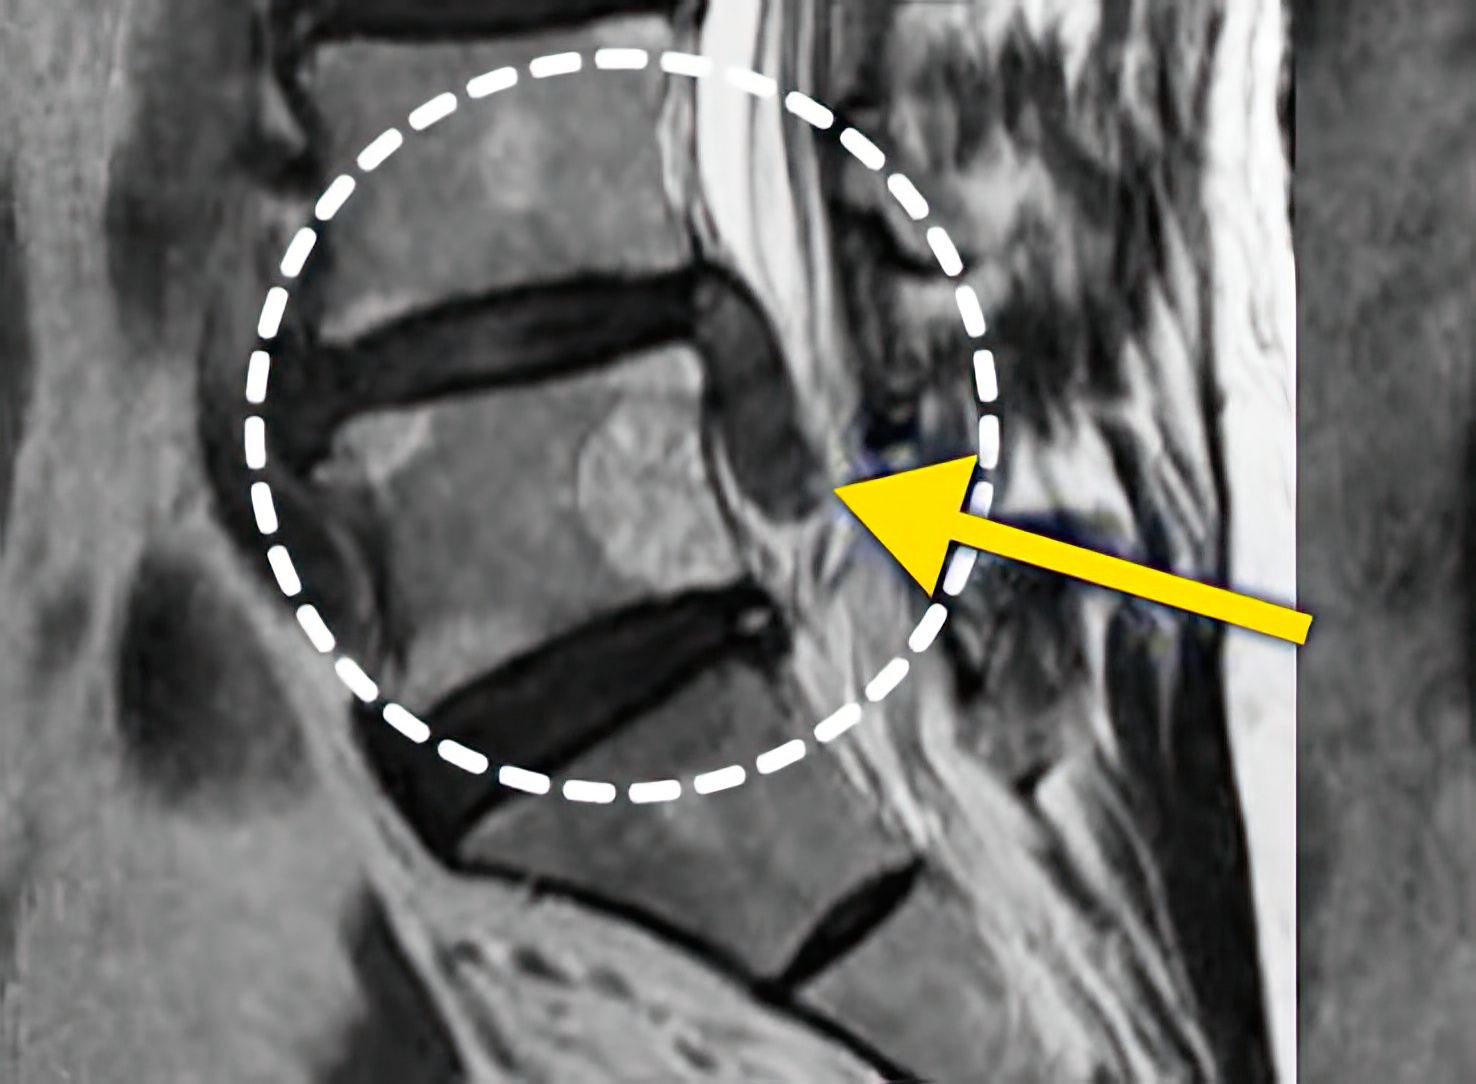

자생 비수술 한방통합치료 후

터진디스크가 흡수된 모습

Before

After

비수술 치료만으로

터진 디스크 흡수

치료 후 탈출된 디스크가

지속적으로 흡수되어 10년 후 2/3 감소